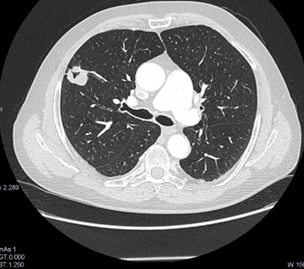

TC de tórax con contraste IV